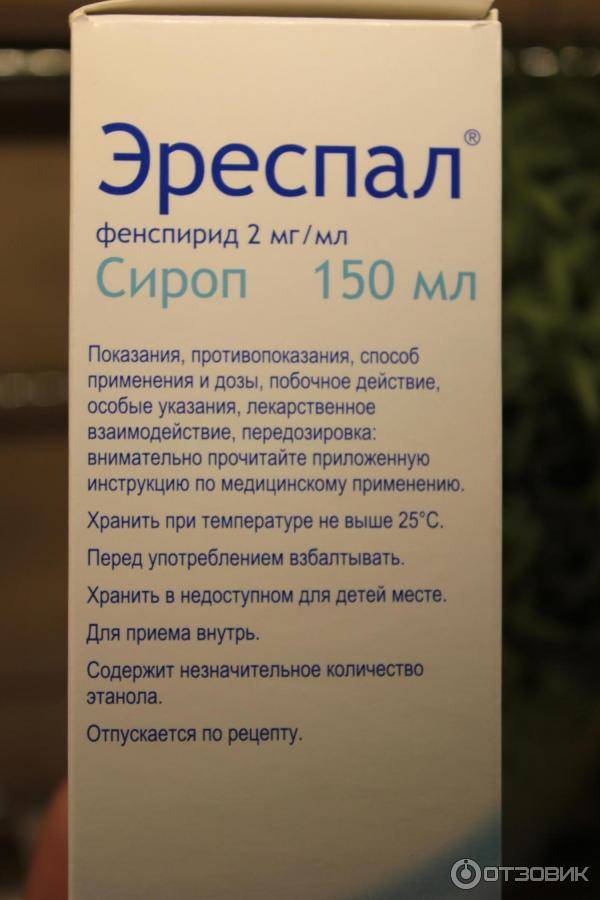

Эреспал детям